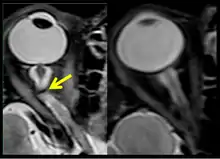

The sixth case of visual changes of an ISS astronaut was reported after return to Earth from a 6-month mission. When he noticed that his far vision was clearer through his reading glasses. A fundus examination performed 3 weeks postflight documented a grade 1 nasal optic-disc edema in the right eye only. There was no evidence of disc edema in the left eye or choroidal folds in either eye (Figure 13). MRI of the brain and eyes days postflight revealed bilateral flattening of the posterior globe, right greater than left, and a mildly distended right optic nerve sheath. There was also evidence of optic-disc edema in the right eye. A fundus examination postflight revealed a "new onset" cotton-wool spot in the left eye. This was not observed in the fundus photographs taken 3 weeks postflight.[3]